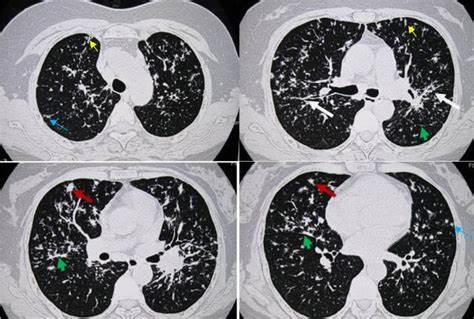

多發(fā)的肺部結(jié)節(jié)確實(shí)越來越多。許多患者很焦慮,對醫(yī)生的臨床決策也是一種考驗(yàn),需要把握好尺度是否為手術(shù)適應(yīng)癥,考慮到患者耐受和肺功能損傷,做手術(shù)能否一起切掉,比如一個(gè)肺葉內(nèi)三個(gè)結(jié)節(jié),切一個(gè)肺葉就能解決;但更多的是左、右肺都有,在切不干凈的情況下,需要確定哪個(gè)是主病灶,可能會(huì)帶來轉(zhuǎn)移等危害,要把最嚴(yán)重的、最危險(xiǎn)的優(yōu)先解決掉。如果病人有許多結(jié)節(jié),且在現(xiàn)階段醫(yī)療水平切不干凈,無法解決根本問題的情況下,等主病灶發(fā)展變化時(shí)再動(dòng)它。并不是所有的病灶都是要外科處理,還可以可以考慮放療等方式。

磨玻璃結(jié)節(jié),一般不會(huì)致命,不會(huì)影響患者的預(yù)后,級別再高也就是一個(gè)浸潤性腺癌,不會(huì)在半年一年內(nèi)出現(xiàn)太大的變化,發(fā)展非常緩慢。實(shí)性結(jié)節(jié)可能存在轉(zhuǎn)移傾向,隨訪更需要認(rèn)真對待,縮短隨訪周期,避免漏檢。

磨玻璃結(jié)節(jié)或混雜性的結(jié)節(jié)可能是原位癌。但這位患者的情況,不能判斷實(shí)性結(jié)節(jié)是否為原位癌。建議這位患者密切隨訪結(jié)節(jié)變化,有變化的話,可以手術(shù),或者SBRT,根據(jù)患者全身情況來判斷,做手術(shù)要考慮到患者的生活質(zhì)量,做這個(gè)手術(shù)是不是獲益。沒有必要對這么小的結(jié)節(jié)進(jìn)行穿刺,即使是導(dǎo)航也不一定能穿到陽性的結(jié)果,隨訪即可。